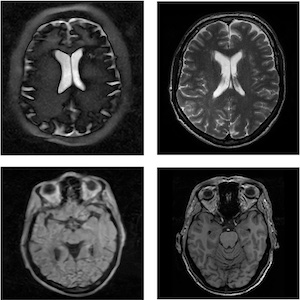

صورة مأخوذة بجهاز تصوير بالرنين المغناطيسي منخفض المجال مقارنة بصورة مأخوذة بجهاز الرنين المغناطيسي التقليدي.

Credit: Leiden University Medical Center

ويستطيع كلا الجهازين حاليًا تصوير الدماغ بوضوح لكل ملليمترين تقريبًا في 10 دقائق. وبالمقارنة، فإن جهاز التصوير بالرنين المغناطيسي التقليدي يمكنه تحليل بنى يقل حجمها عن ملليمتر واحد في بضع دقائق قليلة. وعلى الرغم من أن أداء الأجهزة منخفضة المجال يفي بالغرض في الحالات الواضحة مثل استسقاء الرأس، فمن الممكن تحسينه. وينبغي للباحثين تصميم أجهزة كشف أكثر دقة، وتعزيز تباين الصور، واستخدام أساليب متقدمة لبناء الصور، باستخدام الذكاء الاصطناعي، على سبيل المثال. كذلك ينبغي لهم الحرص على عمل الأجهزة على نحو موثوق بحيث تعطي نتائج راسخة ومحكمة، في الظروف البيئية الصعبة المرجح مواجهتها، في البيئات الريفية في الدول ذات الدخل المتوسط أو المنخفض، على سبيل المثال.